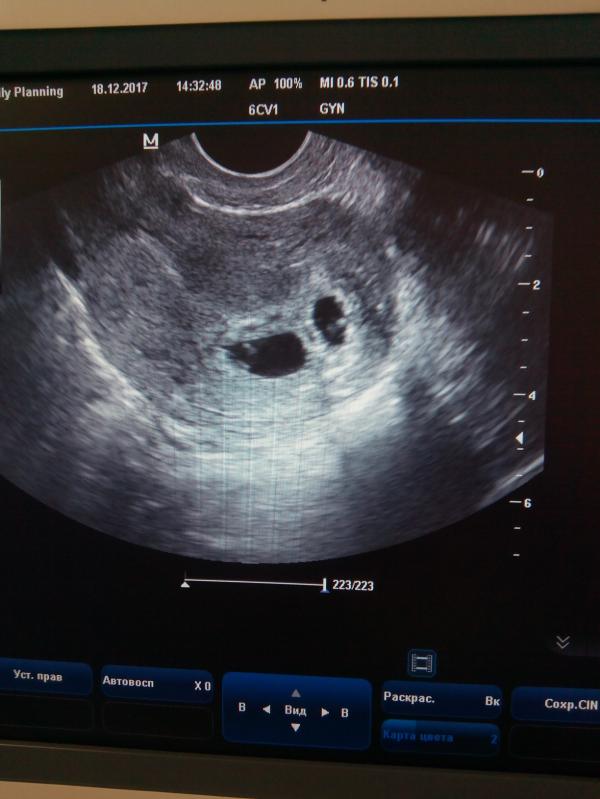

Ура наше первое УЗИ 😍 знакомство с нашими малышами)) все у нас хорошо) все соответствует сроку) двойня как и предполагал врач) Дай бог чтоб беременность была легкой 🙌😍